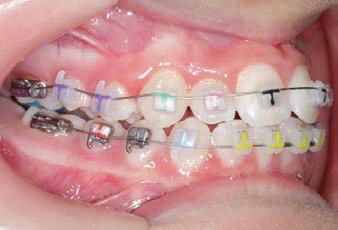

CLASS II DIV.1 - Marra

PROGRESS 1 - 26/9/18 - Class I platform accomplished in 5.75 months with Motion 3D COLOR Appliance

PROGRESS 2 - 26/9/18 - Placement of the SLX 3D Clear Brackets

with M-ONE .015 Cu Nitanium 27°

PROGRESS 3 - 30/10/18 - With M-TWO .020 x .020 Cu Nitanium 35° archwire

PROGRESS 4 - 27/11/18 - 3 links power chain: 5, 4, bypass 3 to crimp hooks

PROGRESS 5 - 13/3/19 - With M-TWO .020 x .020 Cu Nitanium 35° archwire

PROGRESS 6 - 1/8/19 - With M-THREE.019 x .025 Beta Titanium wire